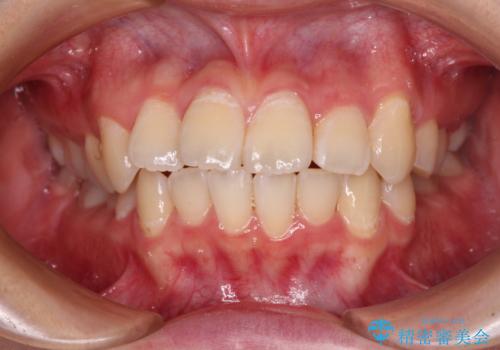

【モニター】八重歯と前歯のクロスバイト ワイヤーを併用しインビザラインで矯正治療

- 前歯のデコボコと八重歯を気にして来院された患者様です。

インビザラインでの治療を希望されていましたが、前歯のクロスバイトや下顎小臼歯の捻転が認められたため、インビザライン単独で治療を行うよりも、ワイヤー装置を併用した方が、治療期間の短縮やトラブル回避できると判断し、ワイヤー装置を併用することとしました。

まずはワイヤー装置により前歯のクロスバイトと下顎小臼歯の捻転を改善し、その後インビザラインにより全体を整える矯正治療を行うこととしました。